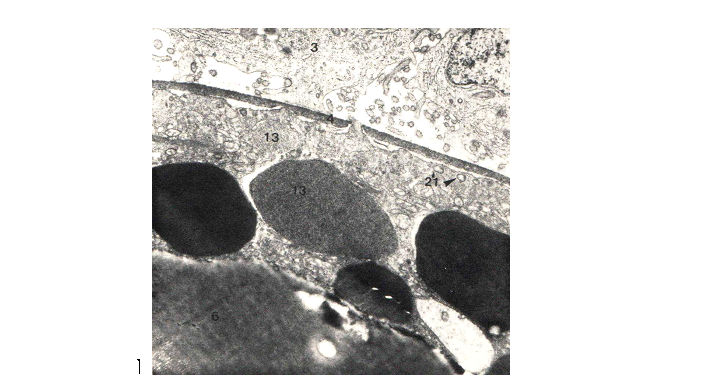

شکل 6: توده های نانوذرات میوفر(13) درون سلولهای تکا فولیکولی در مجاورت بازال لامینا (فلش سیاه)، کورتکس رادیاتوس (فلش قرمز) وفولیکل اپیتل بین این دو. 14 روز پس از تزریق. درشتنمائی : x5700 .

پخش میوفر در جنین در اعضاء مختلف متفاوت است و بخش اعظم آن در اندامهای خونساز ذخیره می گردد(11) (Forth,  et al). 8 روزپس از تزریق ، اندامکهای ذخیره ای حتی درسلولهای عضلانی و همراه (Satelleites ) جنین در حال رشد از نانوذرات میوفر انباشته شده اند (شکل5) بعد از 30 روز تغییری درمقدارذخایر نانوذرات آهن در اووسیت ها و تخمدان و اعضاء ماهی به چشم نمی خورد و فقط در جنین ذخیرۀ اندک آهن ادامه می یابد. این ذخایر در سلول های تخمدان بصورت واحد های مدور با تراکم متفاوت مشاهده می شوند. نانوذرات میوفر تقریبا بیشتر فضای سلولی را به شکل سیتو زومهای با اندازه های تقریبی 3/0 تا 7 میکرون پر می کند. در کبد قسمت اعظم فضای درونی سلول انباشته از میوفر است. تغییرات سیتولوژیکی در مادر بصورت کوتاه شدن میکروویلی ها در سلولهای کبدی وافزایش فضای بین سلولی مشاهده می شود(شکل5-7). سیستم رتیکولو اندوتلیال در طحال به مقدار قابل توجهی میوفر ذخیره می کند.(شکل7) .( 12،13) Granick1946, Greenberg1955 نشان دادند که آهن به محض ورود به سلول به آپوفریتین یک  ناقل آهن متصل می گردد. در جنین پس از 25 روزبزرگی ذخایر میوفر در مقایسه با تخمدان کمتر است(شکل 7). هپسیدین یک پپتید 25 اسید آمینهای که در کبد سنتز می شود نقش تعیین کننده ای در متابولیسم آهن دارد.  مقدار کم هپسیدین یک عامل مهم انباشتگی آهن در بدن یا بروز اختلاتلات ایمنی مخصوصا در بیماری های کبدی می باشد(14،15 )(Thomas et al2005، Nemett et al.2004)